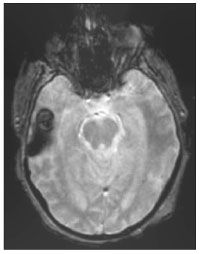

On the third hospital day, gadolinium MRI of the brain performed to evaluate anisocoria revealed a dominant 1.1 x 1.7-cm lesion with surrounding edema. Heme-sensitive sequencing demonstrated susceptibility artifacts around the lesion in the right temporal lobe consistent with associated hemorrhage (Figure 1). Subtle enhancement was also present, although no intense enhancement for pre-T1 hyperintense characteristics was seen (Figure 2, A and B). This dominant lesion was hyperintense on T2-weighted images consistent with surrounding edema and central hypointensity (Figure 2, C). This lesion also showed a smaller internal area of T2 hyperintensity that was not hyperintense on T1-weighted images. In addition, multiple tiny hemorrhagic lesions without marked edema were scattered throughout the cerebral white matter, notably in the corticomedullary junctions (Figure 3, A and B).

Figure 1. Gradient axial MRI scan of the brain revealing a 1.1 x 1.7-cm hemorrhagic mass in the right temporal lobe with surrounding edema and associated hemorrhage.